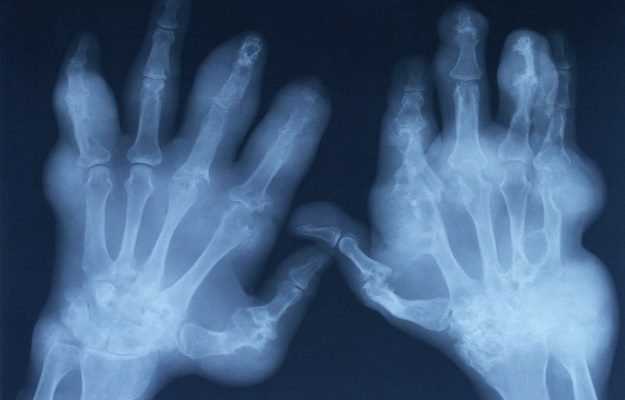

Joint pain, stiffness and swelling are the main signs and symptoms of psoriatic arthritis. They can affect any part of the body, including your fingertips and spine, and can range from relatively mild to severe. In both psoriasis and psoriatic arthritis, disease flares can alternate with periods of remission.

Psoriatic arthritis can affect joints on one or both sides of your body. The signs and symptoms of psoriatic arthritis often resemble those of rheumatoid arthritis. Both diseases cause joints to become painful, swollen and warm to the touch.

A small percentage of people with psoriatic arthritis develop arthritis mutilans — a severe, painful and disabling form of psoriatic arthritis. Over time, arthritis mutilans destroys the small bones in the hands, especially the fingers, leading to permanent deformity and disability.